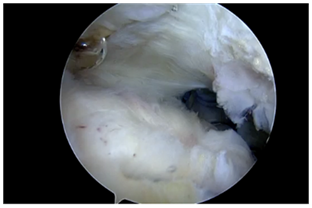

Anchor Bounded hybrid Repair (Figure 4): This technique prioritizes anchors as the primary means of fixation, and allows for the repair of any sized cuff tear with a transosseous equivalent four anchor construct. This repair is typically applied in severely retracted tears, reconstructions, or tears with noncompliant tissue. Anchors are placed at the margins of the tear, securing the mechanically important cables of the rotator cuff, while the intervening tissue is circumferentially opposed to bone with either one or two transosseous tunnels. The tunnels between the anchors respect the biology and bone stock of the tuberosity, while adding additional circumferential compression points of the tendon footprint. Additional tunnels may be created as needed for “dog ears” or further cuff reduction. This paradigm may also be used in superior capsular or graft augmentations, as there are often edges of the graft which must be secured for stability of the graft interface, even after multiple anchors have been used (Figure 5).

Figure 4  Anchor bounded hybrid repair.